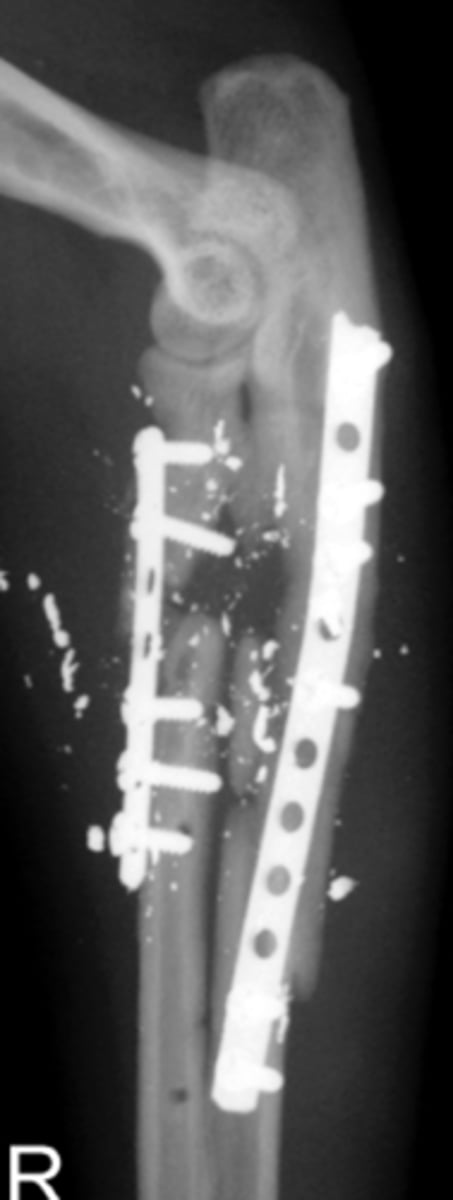

Comminuted fracture

What will most commonly cause a Comminuted fracture ?

Gunshot wound - lots of fragments

All Gun shot wounds will be ____ fractures?